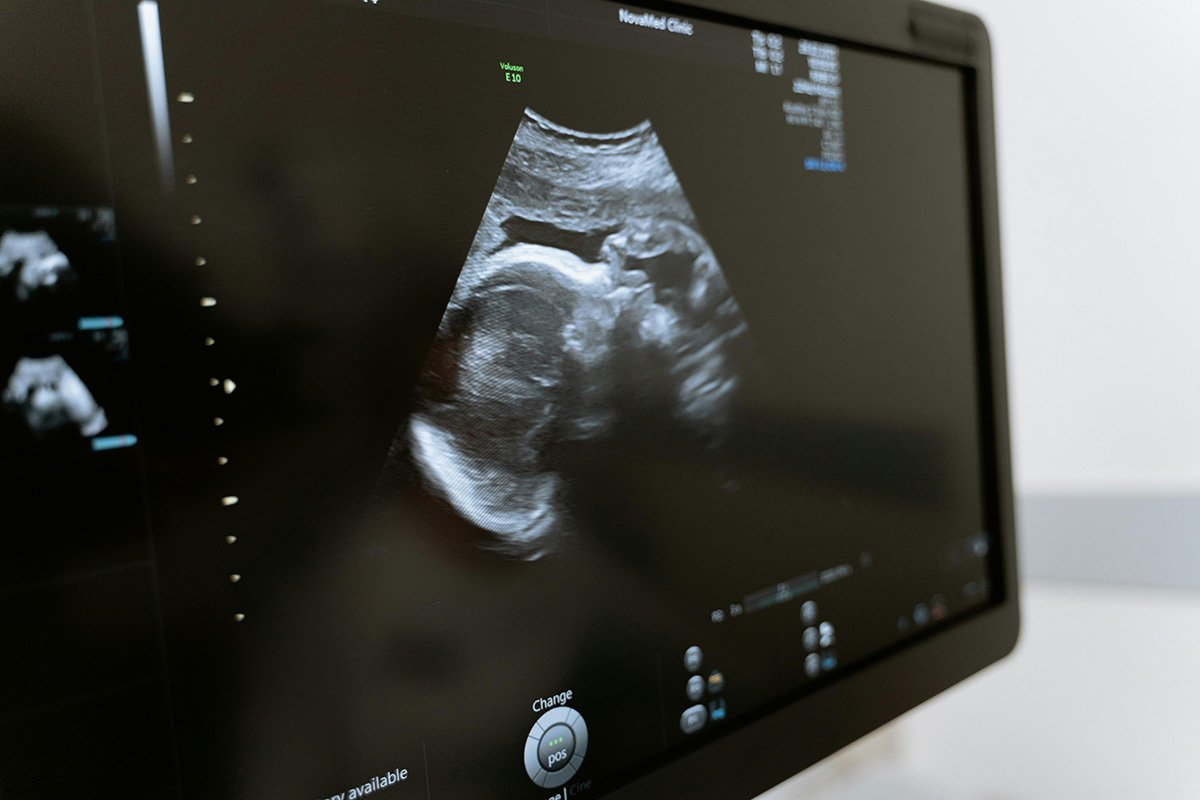

Американский штат Алабама в конце февраля принял беспрецедентное решение, по которому замороженный эмбрион отныне считается человеком и наделяется всеми правами, а его гибель подпадает под закон о противоправных действиях в отношении несовершеннолетнего. Сторонники этого решения считают, что человеческая жизнь считается жизнью с момента зачатия и так же священна, как и жизнь уже родившегося человека. Противники же опасаются, что признание восьмиклеточных микроскопических эмбрионов детьми отодвинет назад все достижения репродуктивных технологий и в перспективе может лишить сотни тысяч людей возможности стать родителями.

В декабре 2020 года одна из пациенток клиники репродуктивной медицины в штате Алабама вошла в отделение криоконсервации и достала емкость с хранящимися в ней замороженными (криоконсервированными) эмбрионами. Поскольку зародыши хранятся при ультраминусовых температурах, пациентка ожидаемо обожглась о лед, отдернула руку и выронила емкость с эмбрионами, которые при ударе разрушились и погибли.

Эмбрионы принадлежали семейной паре, которая несколько лет назад с помощью ЭКО уже родила здорового ребенка, а неиспользованные эмбрионы поместила в криохранилище для возможной будущей беременности.